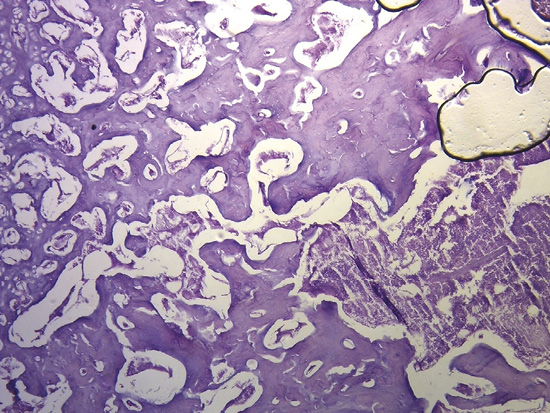

Análisis anatómico e histologíco del miocardio. En la secuencia del análisis histológico del miocardio desplegado (figura 27) se demuestra la orientación longitudinal, de acuerdo con la continuidad de los segmentos que tiene su conformación espacial, tanto en la cara interna como en la externa en cada uno de ellos. Las fibras tienen direcciones paralelas en ambas superficies (interna y externa) de cada uno de los segmentos. La superposición de los segmentos que implica la conformación helicoidal resulta indispensable para lograr la torsión miocárdica, acción fundamental de la mecánica cardíaca que no sería posible con la estructura de malla (entrecruzamiento de fibras miocárdicas). En esta estructura helicoidal se produce un rozamiento en sus superficies de contacto, lo que implica que presenten un sistema lubricante que facilita la movilidad autónoma de ellos con menor gasto de energía, tema que se analizará en esta Proposición.

Figura 27. Secuencia segmentaria del análisis histológico del miocardio continuo. Técnica de hematoxilina-eosina (15x).

Ningún segmento de la histología secuencial en la continuidad longitudinal del miocardio en nuestras investigaciones presentó una disposición en malla. En la cara externa de la parte distal del segmento descendente, al girar a nivel del ápex y transformarse en ascendente, los miocardiocitos generan en los cortes planimétricos una arquitectura disímil a la cara interna en su orientación, único sitio donde sucede esta situación. Esta disposición se halla dada en el ápex, en donde el trayecto en espiral de las fibras miocárdicas que se desplazan desde la periferia hacia el centro determinan un cambio brusco de la dirección, ya que las fibras subepicárdicas se vuelven subendocárdicas (figura 27), superpuestas como las tejas en un techo, que es lo que evidencia la imagen comentada. Esta configuración es lógica para la demostración de la disposición helicoidal pues sucede en el sitio donde el miocardio transforma en forma brusca su dirección de descendente en ascendente. En el resto la disposición es siempre paralela. El miocardio continuo se asemeja a la cinta de Moebius dado el cambio progresivo de la angulación en las fibras transformándose de epicárdicas en endocárdicas (164).

Figura 28. Fibras apexianas (corazón de bóvido).

Esta investigación evidencia que el miocardio no se estructura como una malla sino en forma de músculo continuo en espiral (figura 28) (217). El concepto que se ha esgrimido de malla fue elaborado a partir de la superposición de segmentos a través del plegamiento de la hélice miocárdica. Si se desenrolla el miocardio con la técnica de disección apropiada se obtiene un grosor similar en toda la extensión del músculo, evidenciando que su continuidad es real. Plegado, se encuentra que el grosor del ventrículo derecho es la mitad que la del ventrículo izquierdo, ya que el primero se halla compuesto por solo un segmento del músculo, mientras que el segundo presenta adosamiento de dos segmentos. Su disección, por los planos de clivaje comentados, siempre finaliza en la misma estructura de desplegamiento. La pregunta es la siguiente: ¿cómo es posible repetir disecciones obteniendo siempre el mismo resultado y no concluir en la existencia de una continuidad de las fibras miocárdicas?